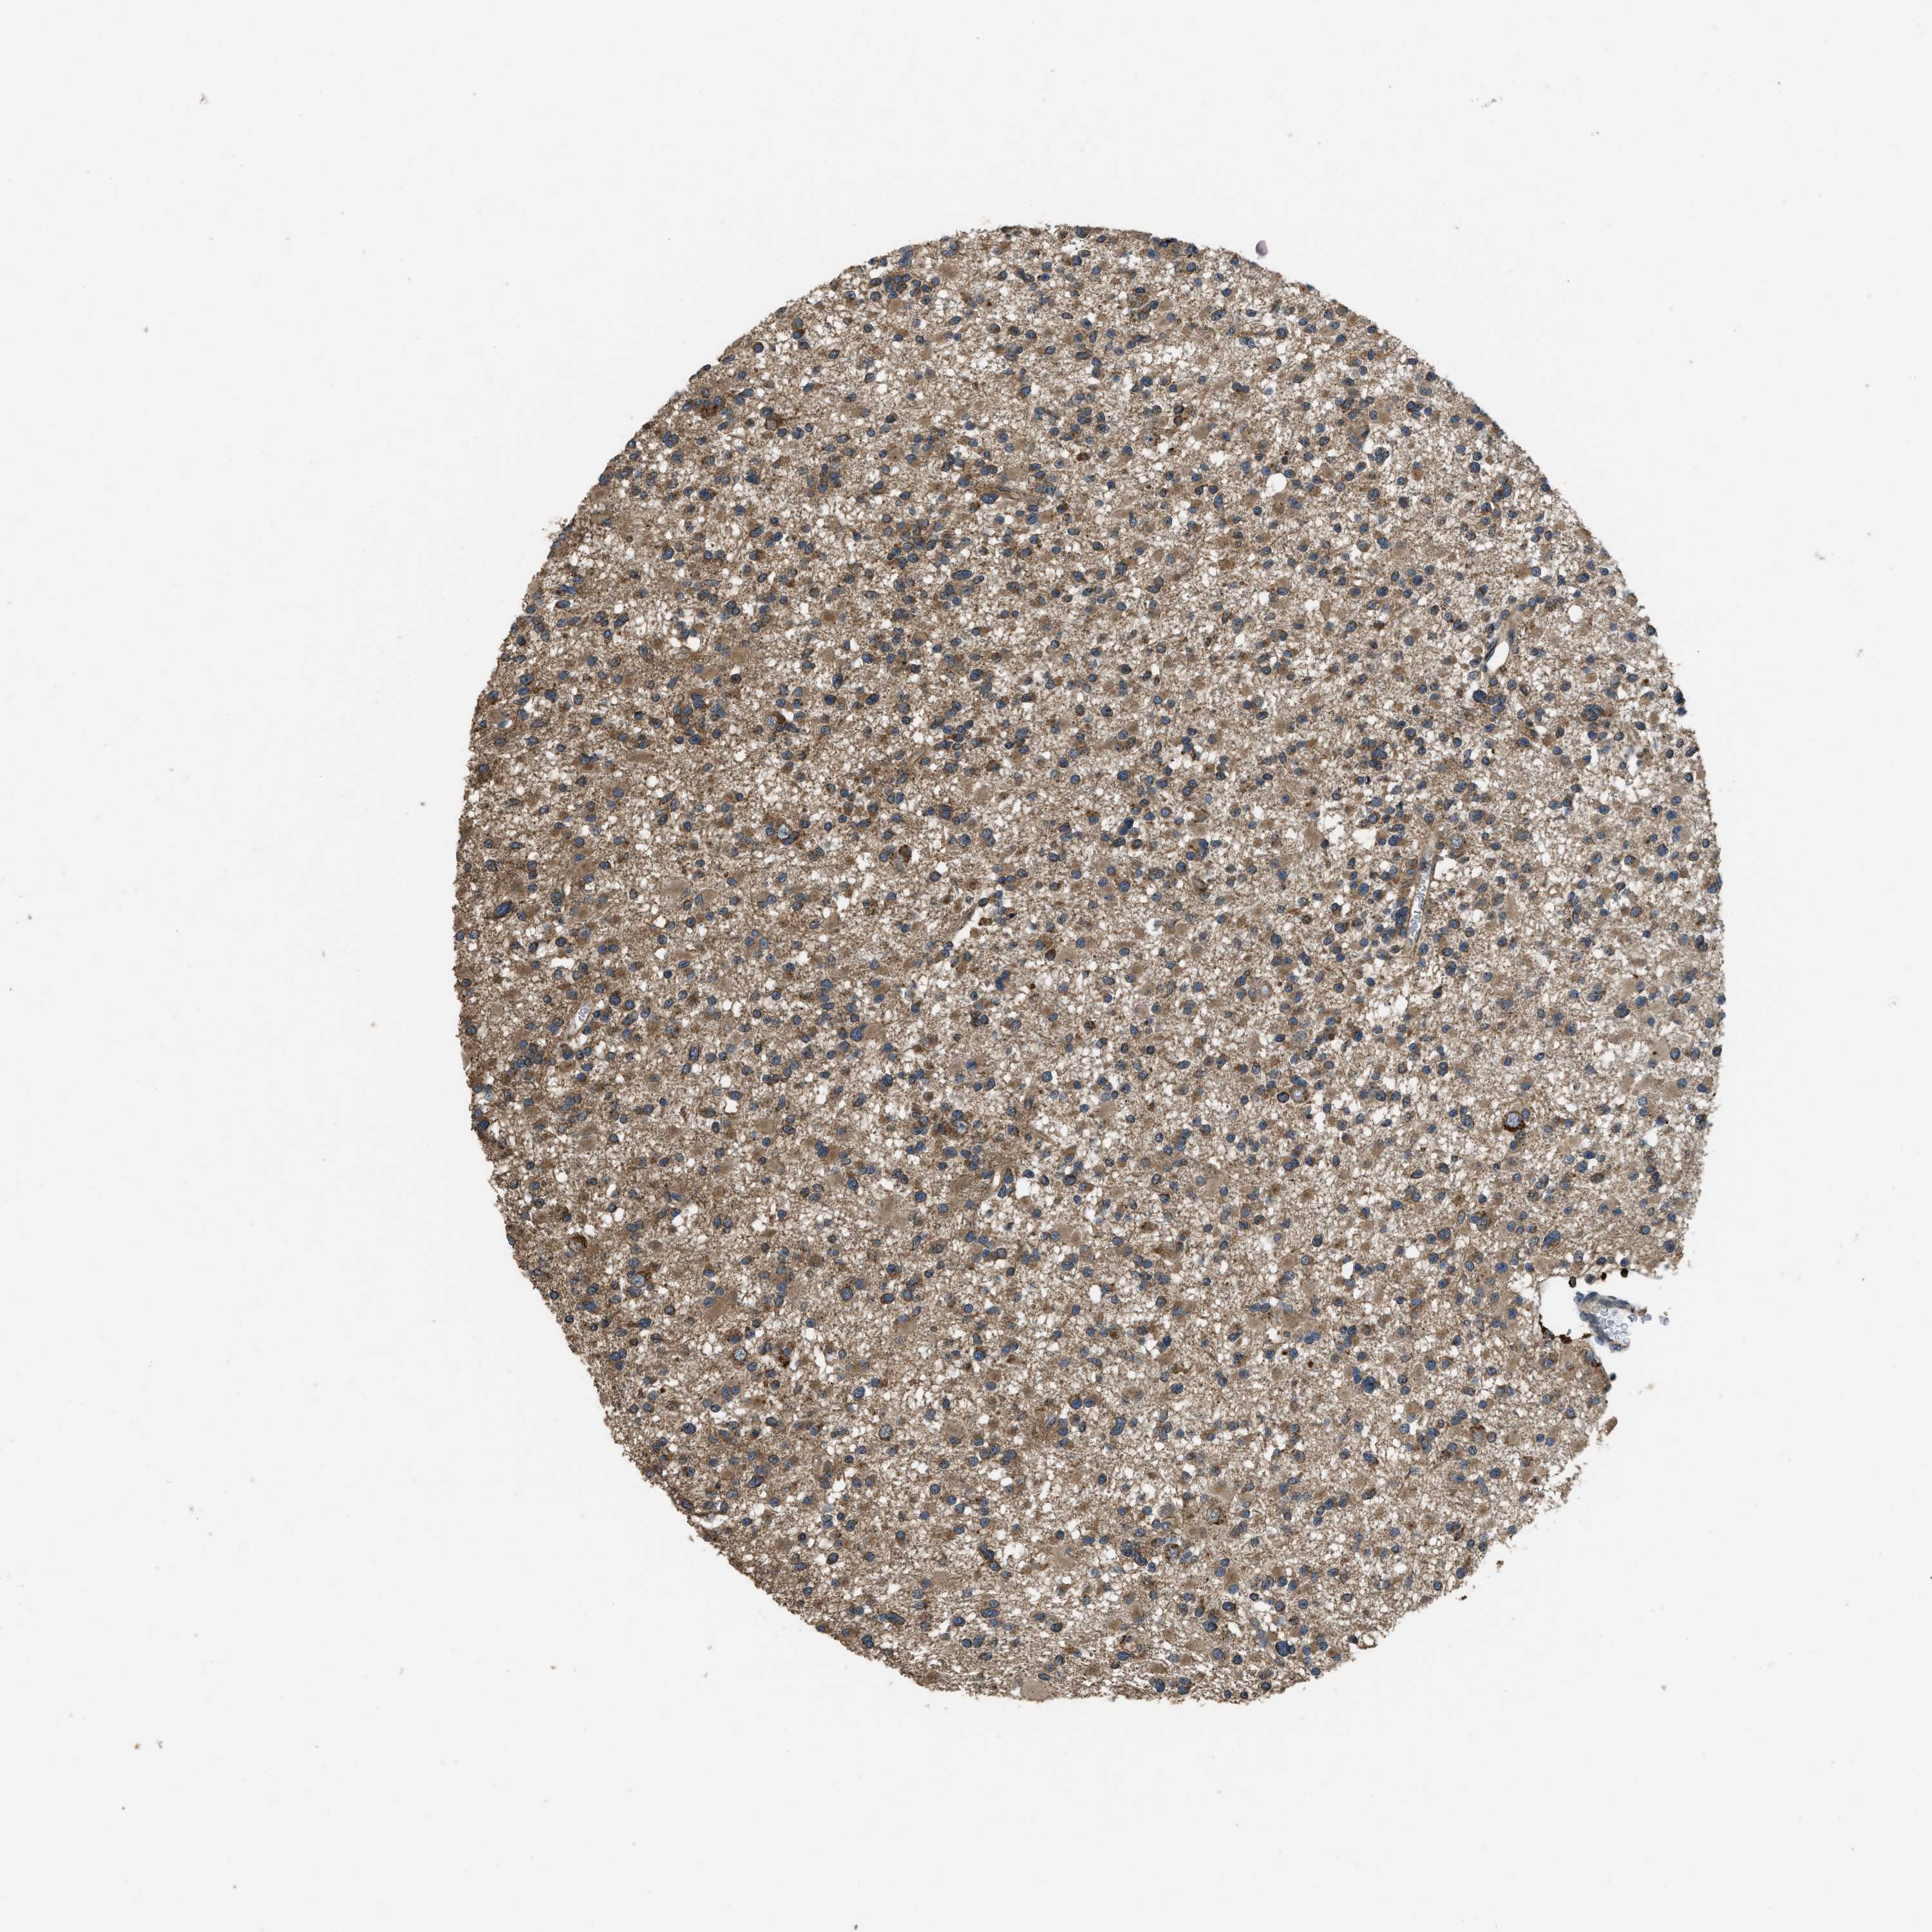

GLIOMA - Protein expressioni

A mouse-over function shows sample information and annotation data. Click on an image to view it in a full screen mode. Samples can be filtered based on level of antibody staining by selecting one or several of the following categories: high, medium, low and not detected. The assay and annotation is described here.

Note that samples used for immunohistochemistry by the Human Protein Atlas do not correspond to samples in the TCGA dataset.

Antibody stainingi

Antibody staining in the annotated cell types in the current human tissue is reported as not detected, low, medium, or high, based on conventional immunohistochemistry profiling in selected tissues. This score is based on the combination of the staining intensity and fraction of stained cells.

Each image is clickable and will lead to virtual microscopy that enables deeper exploration of all samples and also displays staining intensity scores, fraction scores and subcellular localization as well as patient and tissue information for each sample.

Antibody HPA025226

Antibody CAB019296

Staining

High

Medium

Low

Not detected

Intensity

Strong

Moderate

Weak

Negative

Quantity

>75%

75%-25%

<25%

None

Location

Nuclear

Cytoplasmic/membranous

Cytoplasmic/membranous,nuclear

Glioma, malignant, High grade

Glioma, malignant, Low grade